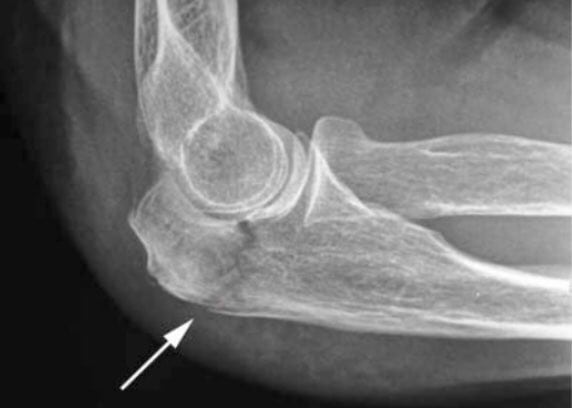

Для диагностирования патологического состояния измеряется объем движений, проводится рентгенография, КТ, МРТ. В терапии контрактуры используются консервативные методики, в том числе физиопроцедуры и ЛФК. При развитии серьезных осложнений пациентам показана хирургическая операция.

Для уточнения диагноза врач изучает анамнез пациента. Подтверждением становится наличие в нем предшествующих травм, воспалительных или дегенеративных суставных заболеваний локтя. Проводится и ряд инструментальных исследований:

- рентгенография для оценки состояния хрящевых и костных тканей;

- МРТ или КТ для обнаружения изменений в соединительнотканных структурах (связках, мышцах, сухожилиях).